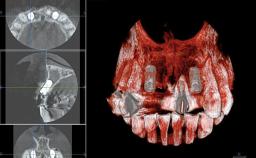

A 38-year-old woman presented with an esthetically unacceptable fixed partial denture replacing teeth 11, 21, 22. She had lost these teeth due to trauma when she was a child. The patient was not in pain but very concerned based on her previous experience that dental treatments had never satisfied her esthetic expectations. She was in good general health and reported no regular medications. No periodontal disease was noted despite the fact that the buccal flange of the prosthesis impeded cleaning of the tooth abutments. The patient did not smoke and complied with home maintenance requirements, as evidenced by her good oral hygiene status.

Bone Volume | Deficient horizontally, requiring prior grafting |